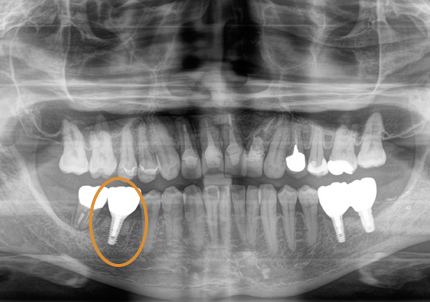

18.インプラント埋入後 パノラマレントゲン

5.インプラント埋入(2021年6月)

※ 初期固定35N/cm確認する

8.補綴物完成(埋入後5か月)

9.左下3本最終補綴装着(2021年11月)

10.口腔内写真(2022年2月)

特に問題無く経過はとても良いです。

患者様ご本人も「良く咬めてとても良い」と満足されています。

11.口腔内写真(2025年6月)

右下2本初診より9年経過、左下3本埋入後4年経過、ともに経過良好。

↑ 初診時パノラマレントゲン(2023年4月1日)

↑ 右下6番最終補綴物セット時パノラマレントゲン(2025年4月22日)